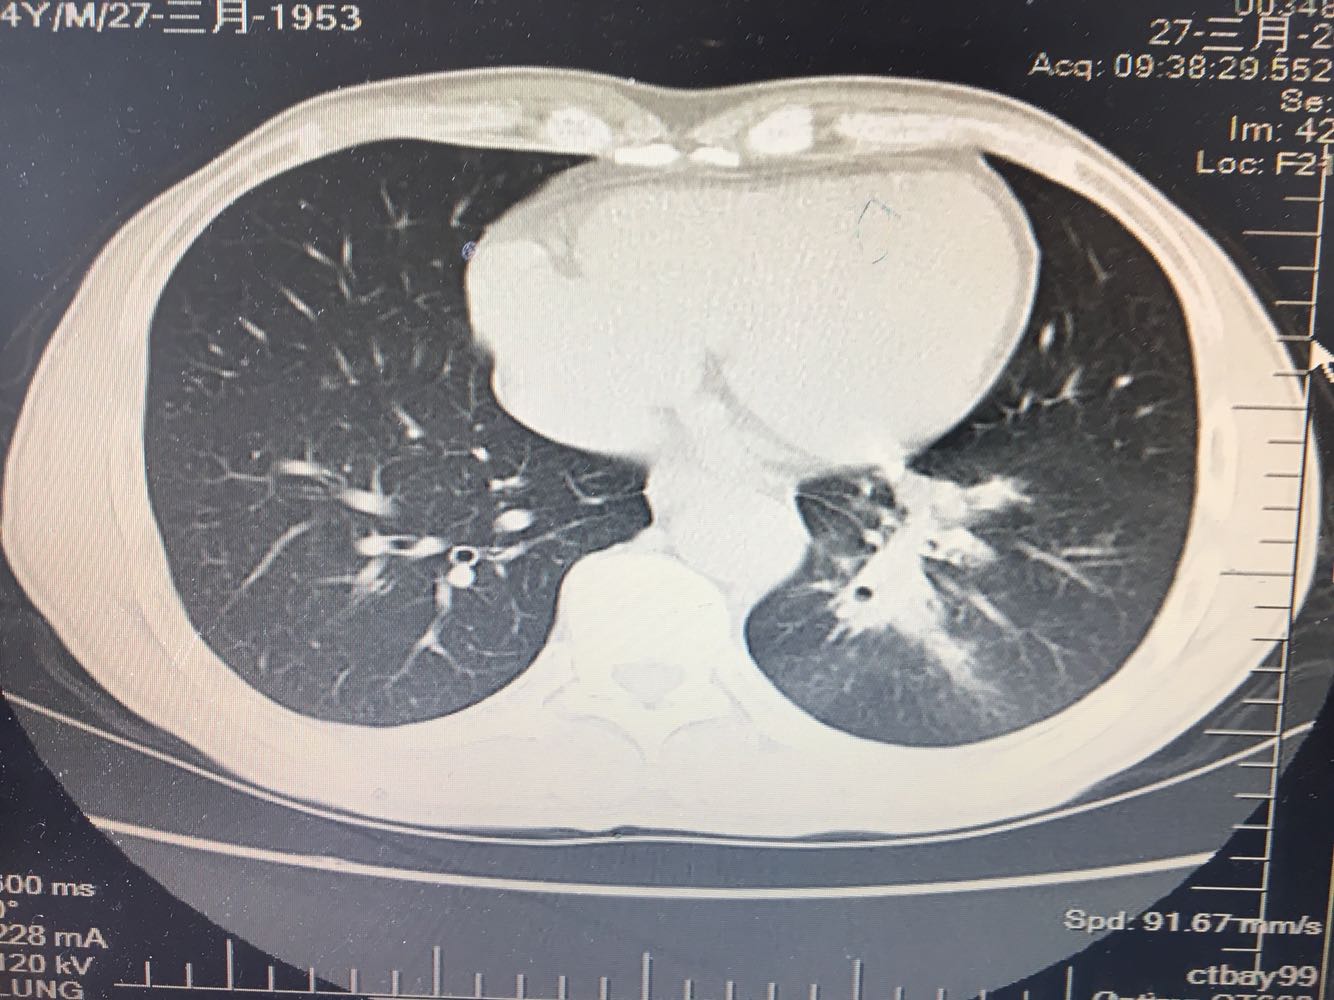

左肺下叶鳞癌

男,63岁,咳嗽1个月入院,患者自述1个月前无诱因咳嗽,阵发性干咳,无痰,时有血丝,无发热,左胸痛,活动后气短,静滴头孢13天无好转,门诊查肺CT后以 肺占位收入我科,病来饮食睡眠可,体重明显下降。既往疝气术后1年,吸烟史30年,每日1包。

左肺癌

左肺中央型肺癌,是否可以手术,还是化疗,放疗,靶向治疗?